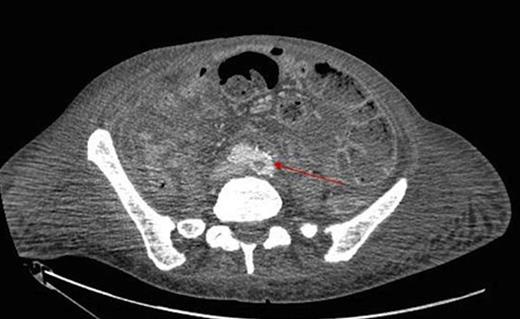

During inpatient stay, she became haemodynamically unstable with spiking temperatures and an elevating white cell count. She also complained of bilateral discolouration of her toes and examination revealed increasing oedema with diminished pedal pulses. A contrast CT scan of the abdomen confirmed ongoing collections with evidence of an aortic thrombus extending into the left iliac artery, presumed to be the embolic source for her vascular findings (figure 2 & 3). She underwent a further laparotomy and washout, and was heparinised postoperatively. There was resolution of vascular symptoms and evidence of improvement in peripheral perfusion postoperatively, and the patient was eventually discharged.

Thrombus within the distal aorta shown by a filling defect (red arrow)